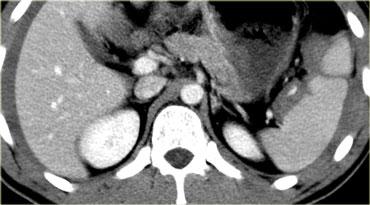

Trước tiên hãy quan sát các hình ảnh bên trái của bệnh nhân bị chấn thương gan.

Các dấu hiệu CT trong trường hợp này là gì?

Các dấu hiệu bao gồm:

- Tụ máu dưới bao gan lớn hơn 10 cm (tức là tổn thương độ 4)

- Vùng ngấm thuốc cản quang (contrast blush) (mũi tên)

- Không có tràn máu ổ bụng kèm theo

Vì vậy, mặc dù có thoát thuốc cản quang, bệnh nhân này sẽ được điều trị bảo tồn (không phẫu thuật) và có thể có tiên lượng tốt, do không có chảy máu vào khoang phúc mạc.

Thoát thuốc cản quang có ý nghĩa đặc biệt quan trọng, nhất là khi kết hợp với tràn máu ổ bụng.